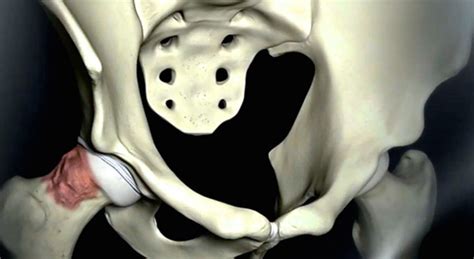

First things first: what exactly is femoroacetabular impingement ? In a nutshell, FAI is a condition where the bones of the hip joint don’t fit together perfectly. This mismatch causes them to rub against each other during movement. Over time, this repeated friction can damage the cartilage (the smooth, cushioning tissue) that lines the joint, as well as the labrum (a ring of cartilage that helps stabilize the hip). The term “impingement” refers to the abnormal contact between the femur (thigh bone) and the acetabulum (the socket of the hip joint). This abnormal contact leads to pain and restricted movement. It can significantly impact a person’s quality of life, making everyday activities like walking, sitting, and exercising painful and difficult. Untreated FAI can lead to early-onset osteoarthritis, which is essentially the breakdown of the joint cartilage, causing further pain and disability. Therefore, recognizing the signs and symptoms early on is very important, as is understanding the various treatment options available. Early intervention can often prevent the progression of the condition and maintain a good hip function for a longer period of time. It’s crucial to understand the mechanism behind the impingement in order to choose the appropriate treatment for the patient. Ultimately, the goal is to alleviate pain, improve function, and slow down the progression of any associated damage.

There are generally three main types of FAI, and it’s not unusual for people to have a combination of them. Understanding these types is key to grasping the specific mechanics of the condition:

- Cam Impingement: This type is characterized by an abnormally shaped femoral head (the ball part of the hip joint). It’s often due to an excess of bone on the femoral head. As the hip moves, this bump jams against the acetabulum, leading to the impingement. This type is more common in young, athletic men. The abnormal shape limits hip rotation and often causes a “pinching” sensation, especially during activities that involve hip flexion and internal rotation.

- Pincer Impingement: In pincer impingement, the problem lies with the acetabulum (the socket part of the hip). There is an overgrowth of bone around the rim of the acetabulum, causing it to excessively cover the femoral head. When the hip moves, the labrum is crushed between the femoral head and the acetabular rim. This type is more prevalent in middle-aged women. Symptoms can include a deep, aching pain in the groin area and a feeling of catching or clicking in the hip.

- Mixed Impingement: As the name suggests, this is a combination of both cam and pincer impingement. This is the most common presentation of FAI. In these cases, there are abnormalities in both the femoral head and the acetabulum, leading to a complex and often severe form of impingement. Treatment strategies must address both the bony abnormalities to restore the normal mechanics of the hip joint.